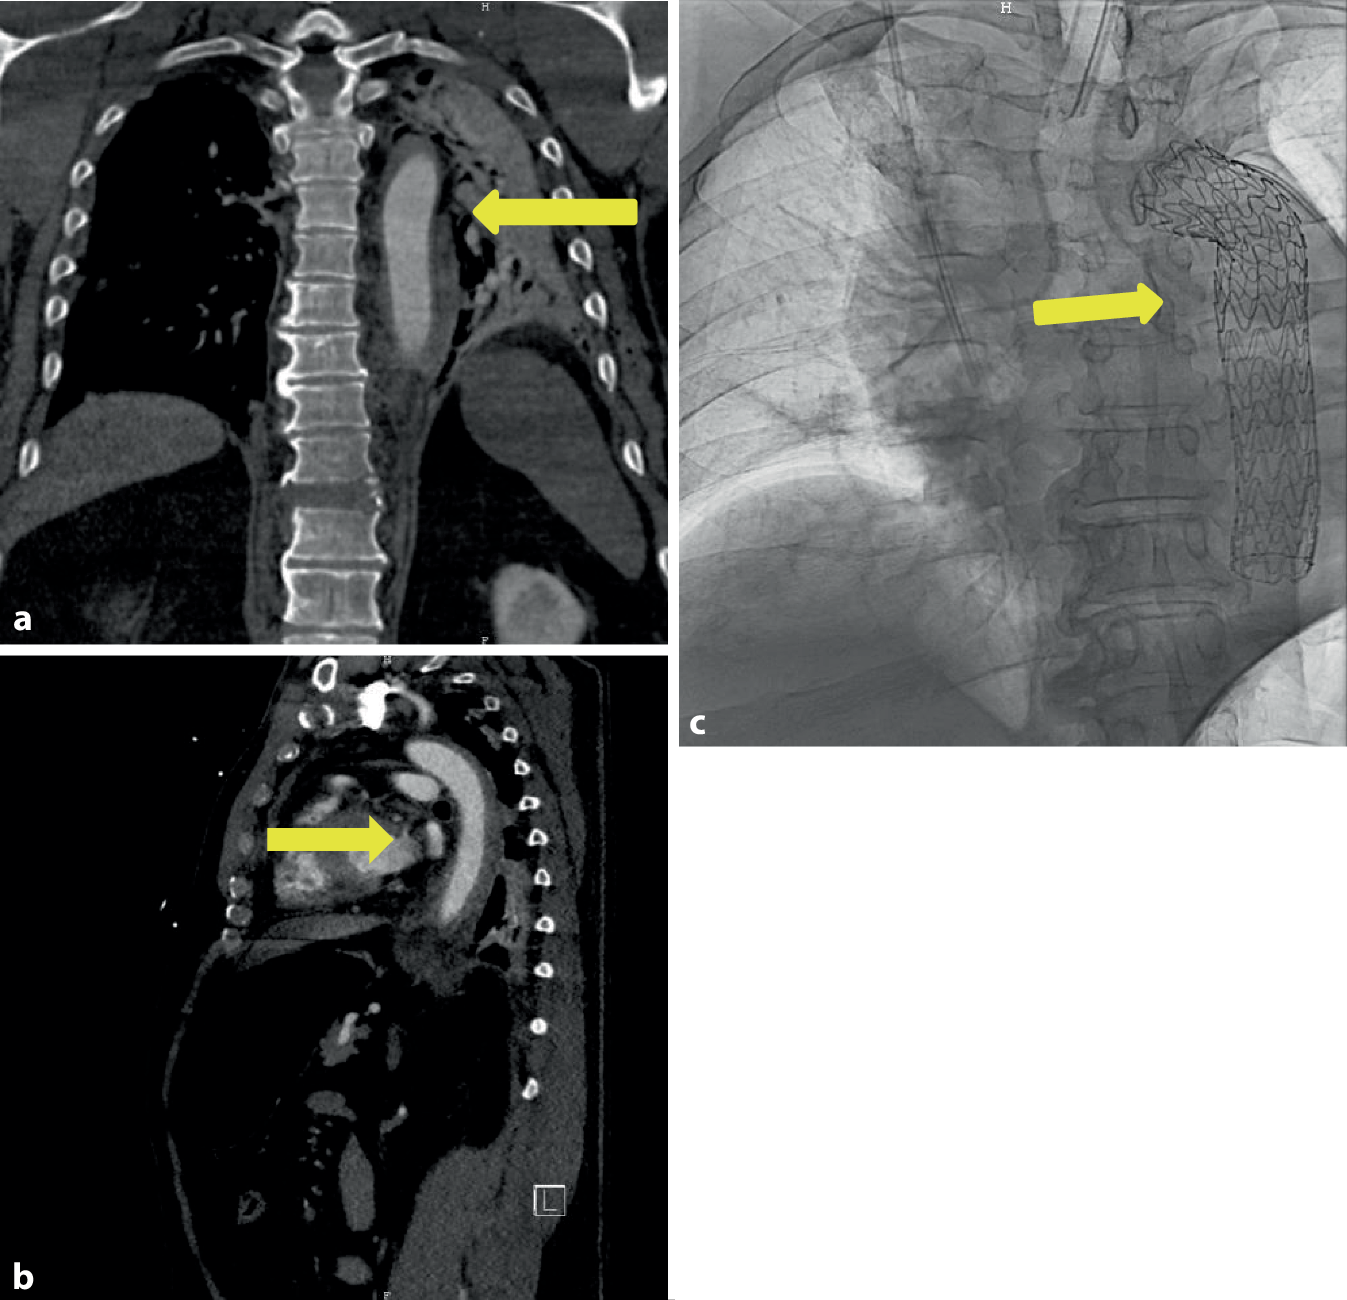

Die initiale Sonographie zeigte eine 7,1 × 7,2 cm echoleere Raumforderung mit echoreichen Thrombusformationen, in der farbcodierten Duplexsonographie mit einer pulssynchronen vollen Farbfüllung. Die konventionelle Nativröntgenuntersuchung der linken Schulterregion (und) die Knochenrekonstruktion einer Nativcomputertomographie (CT) dokumentierten eine ausgedehnte Osteolyse der Klavikula im mittleren Drittel, die eine Längsausdehnung von ca. 5–6 cm im Vergleich zur Gegenseite einnahm (Abb. 1a). Es ließ sich eine ausgedehnte Weichteilschwellung mit einem Durchmesser von 103 mm in dieser Region nachweisen (Abb. 1b). Die nachgeschaltete CT-Angiographie (CTA) zeigte im Bereich der linken Schulter ein ca. 8,6 × 7 cm großes Pseudoaneurysma, entspringend aus der A. subclavia sinistra, welches die Umgebungsstrukturen verdrängte (Abb. 1c).

Abb. 1

Fall 1: Pseudoaneurysma der A. subclavia links. a 3-D-Rekonstruktion des linksthorakalen CT-Scans, insbesondere der linken Klavikula mit Osteolyse im mittleren Drittel (gelber Pfeil), b präoperative Darstellung des linksklavikulären Lokalbefundes mit raumfordernder Wirkung (gelber Pfeil), c CT-Angiographie (transversale Schichtung) mit Nachweis des Pseudoaneurysmas links (gelber Pfeil), d digitale Subtraktionsangiographie der A. subclavia sinistra mit Nachweis des Pseudoaneurysmas (mattgrau – gelber Pfeil)

Der 58-jährige Patient fuhr mit seinem LKW gegen ein Hindernis und musste von der Feuerwehr geborgen werden. Im Rahmen des Unfalls zog er sich folgende Verletzungen zu: eine gering dislozierte Fraktur der Okzipitalkondyle links, eine kleine Kontusionsblutung temporal und basofrontal links, eine diskrete Subarachnoidalblutung hochparietal rechts, eine Rippenserienfraktur rechtsdorsal, eine Sternumfraktur, eine instabile Zerreißungsfraktur von Brustwirbelkörper (BWK) 10 mit Beteiligung des Bandscheibenfaches BWK 10/BWK 11, eine Kompressionsfraktur des Lendenwirbelkörpers (LWK) 1, eine mehrfragmentäre Fraktur des Azetabulums links, eine symphysennahe Fraktur des unteren Schambeinastes sowie eine traumatische Aortendissektion an loco typico des Aortenisthmus. Nach Sicherung der Aortendissektion in der Traumaspirale und einer CT-Angiographie (Abb. 6a, b) des Schockraumes erfolgte die zeitnahe Versorgung der Dissektion in der Angio-Suite mittels einer Stentprothese (Gore TAG Conformable® 28 × 28 × 150 mm, W. L. Gore & Associates, Inc.) über einen Leistenzugang rechtsseitig, beginnend am Abgang der A. subclavia links. Somit wurde das wahrscheinliche „Entry“ an typischer Stelle abgedeckt. Postoperativ blieb der Patient weiter stabil intubiert und beatmet, sodass die weitere Versorgung der Verletzungsfolgen vorgenommen werden konnte.

Abb. 6

Fall 6: Traumatische Dissektion/Hämatom der Aorta thoracica nach Verkehrsunfall. a CT-Angiographie mit koronarer Darstellung des Aortenwandhämatoms (gelber Pfeil), b CT-Angiographie mit sagittaler Darstellung des Aortenwandhämatoms (gelber Pfeil), c Nativröntgenbild des Aortenstents (gelber Pfeil)